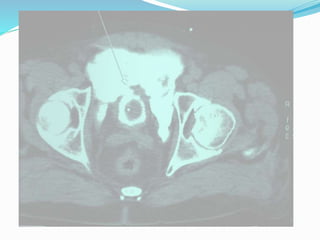

 Cystography (conventional or CT-cystography)

 Fill the bladder with at least 350 mL of dilute contrast

material.

 Computed tomography cystography is preferred in case of

other possible abdominal injuries or causes of abdominal

pain.

 Imperative in case of visible haematuria combined with

pelvic fracture

imaging  Cystography (conventionalor CT-cystography)  Fill the bladder with at least 350 mL of dilute contrast material.  Computed tomography cystography is preferred in case of other possible abdominal injuries or causes of abdominal pain.  Standard evaluation for external trauma and in case of suspicion of an iatrogenic bladder injury in the post- operative setting.  Imperative in case of visible haematuria combined with pelvic fracture